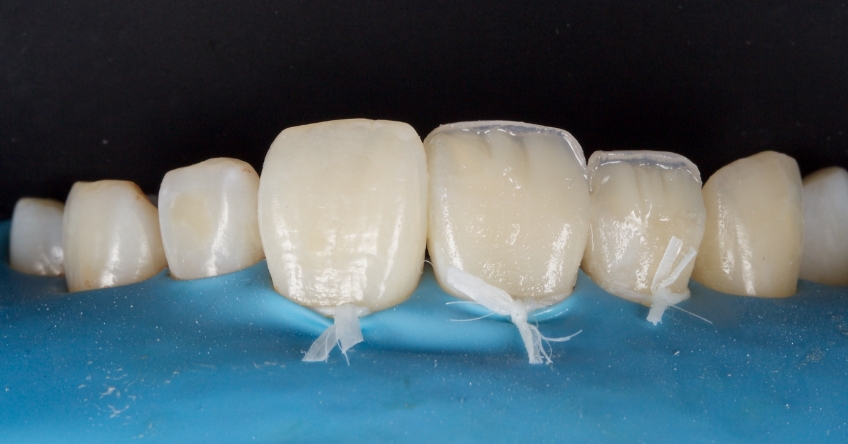

Any biofilm and aprismatic enamel were removed from the tooth, and the fragment was fragmented with light hydro abrasion with 29-micron alumina at 2-3 bar pressure. The tooth and the fragment were etched with 37% phosphoric acid (Ultradent), and a fourth-generation dentin bonding agent (Kerr, OptiBond FL) was applied (the adhesive component was not light-cured).

The fragment was luted to the tooth with heated chromatic enamel shade composite (GC G-aenial A2 shade). The heater used was a Calset Warmer from Addent. The excess composite was cleaned with an interproximal carver from American Eagle and smoothed with a number three brush and modeling resin (Brush & Sculpt from Cosmedent).

The composite was heated because it gained lower viscosity to improve adaptation. Plus, heating increases the conversion of monomer to polymer, which improves the physical characteristics of the resin, such as flexural strength and wear resistance, according to research by Da Costa, Hilton, and Swift in 2011.

The resin was polymerized, and the oxygen-inhibited layer was removed by polymerization under glycerine.